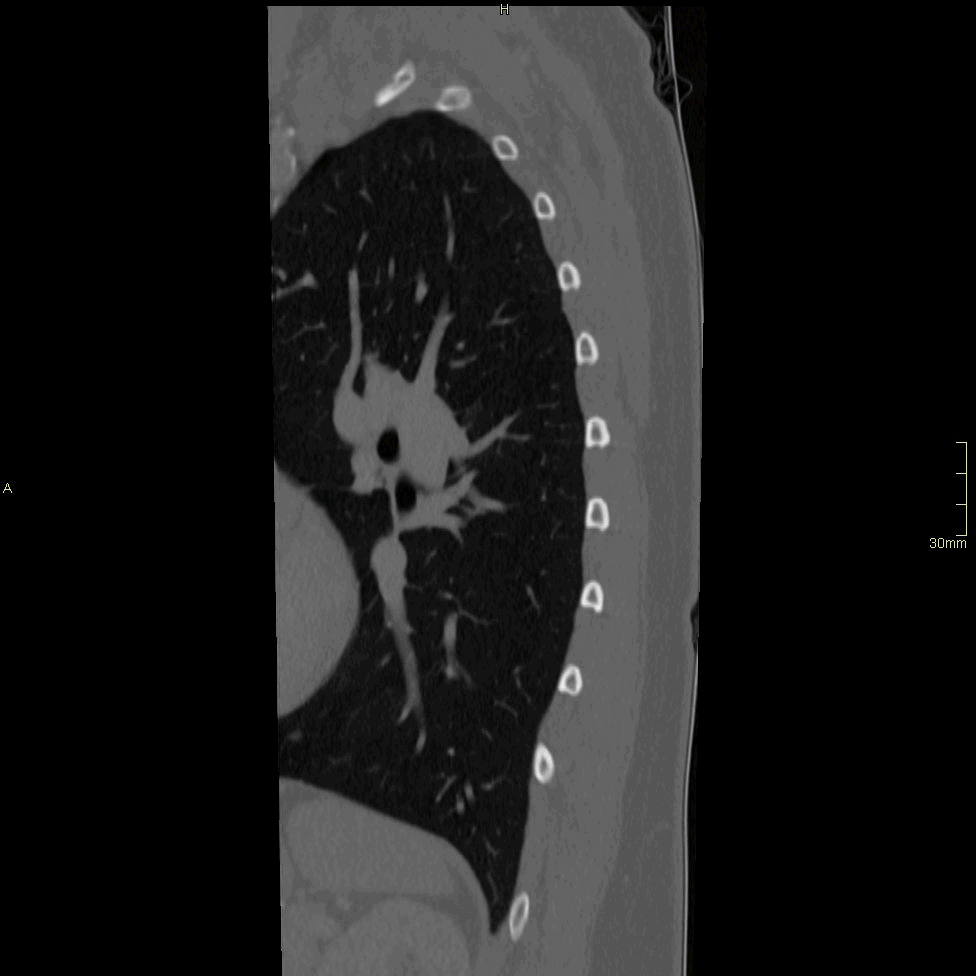

CT Thoracic Spine Contrast- Soft tissue window (axial)

CT Thoracic Spine Contrast- Soft tissue window (coronal)

CT Thoracic Spine Contrast- Soft tissue window (sagittal)

CT Thoracic Spine Contrast- Bone window (axial)

CT Thoracic Spine Contrast- Bone window (coronal)

CT Thoracic Spine Contrast- Bone window (sagittal)